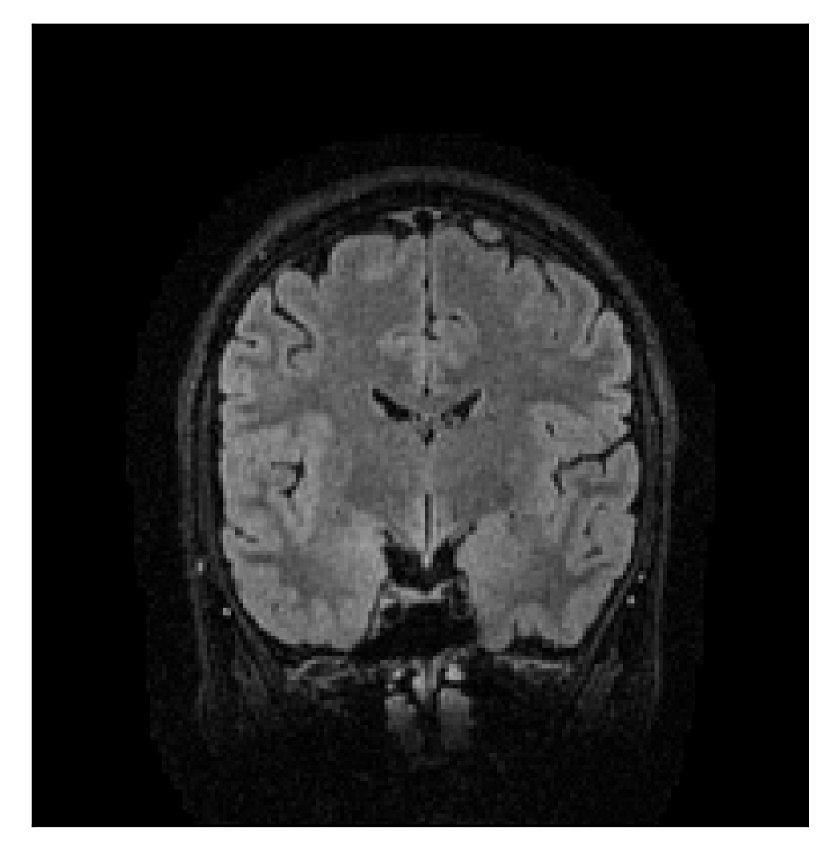

4.1 Experiment 1: robustness test

We gather the results for the robustness test described in Section 3.1 (volunteer 1) in Figures 2, 4, and 6 for motion corruption mechanisms associated to one, two, and five changes of position, respectively. Furthermore, we juxtapose the corrected images with varying degrees of corruption in Figure 8. We observe that the proposed method consistently ameliorates the corrupted scan. The quality indexes based on PSNR and SSIM show only a modest decrease in correction quality as a function of motion complexity (Figure 8).

| Section 3.1, Figure 2 | Sagittal | 23.94 | 27.95 | 0.7068 | 0.7936 |

| Coronal | 26.66 | 29.82 | 0.7653 | 0.8332 | |

| Axial | 25.40 | 30.16 | 0.7616 | 0.8490 | |

| Section 3.1, Figure 2 | T2-FLAIR | Completely corrected | Some blurring | No additional artifacts | Good grey white matter differentiation |

| Section 3.1, Figure 4 | T2-FLAIR | Completely corrected | Some blurring | No additional artifacts | Good grey white matter differentiation |